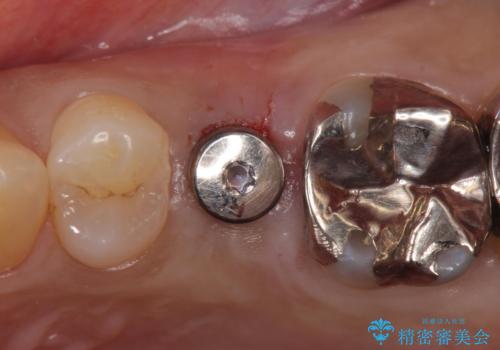

歯茎が腫れる インプラントでの治療

- 40代女性

- 10ヶ月

- 左上5/インプラント:242,000円 骨増生:55,000円 カスタムアバットメント:110,000円 インプラント用仮歯:22,000円 ジルコニアクラウン:121,000円 合計550,000円費用は治療当時の料金となります